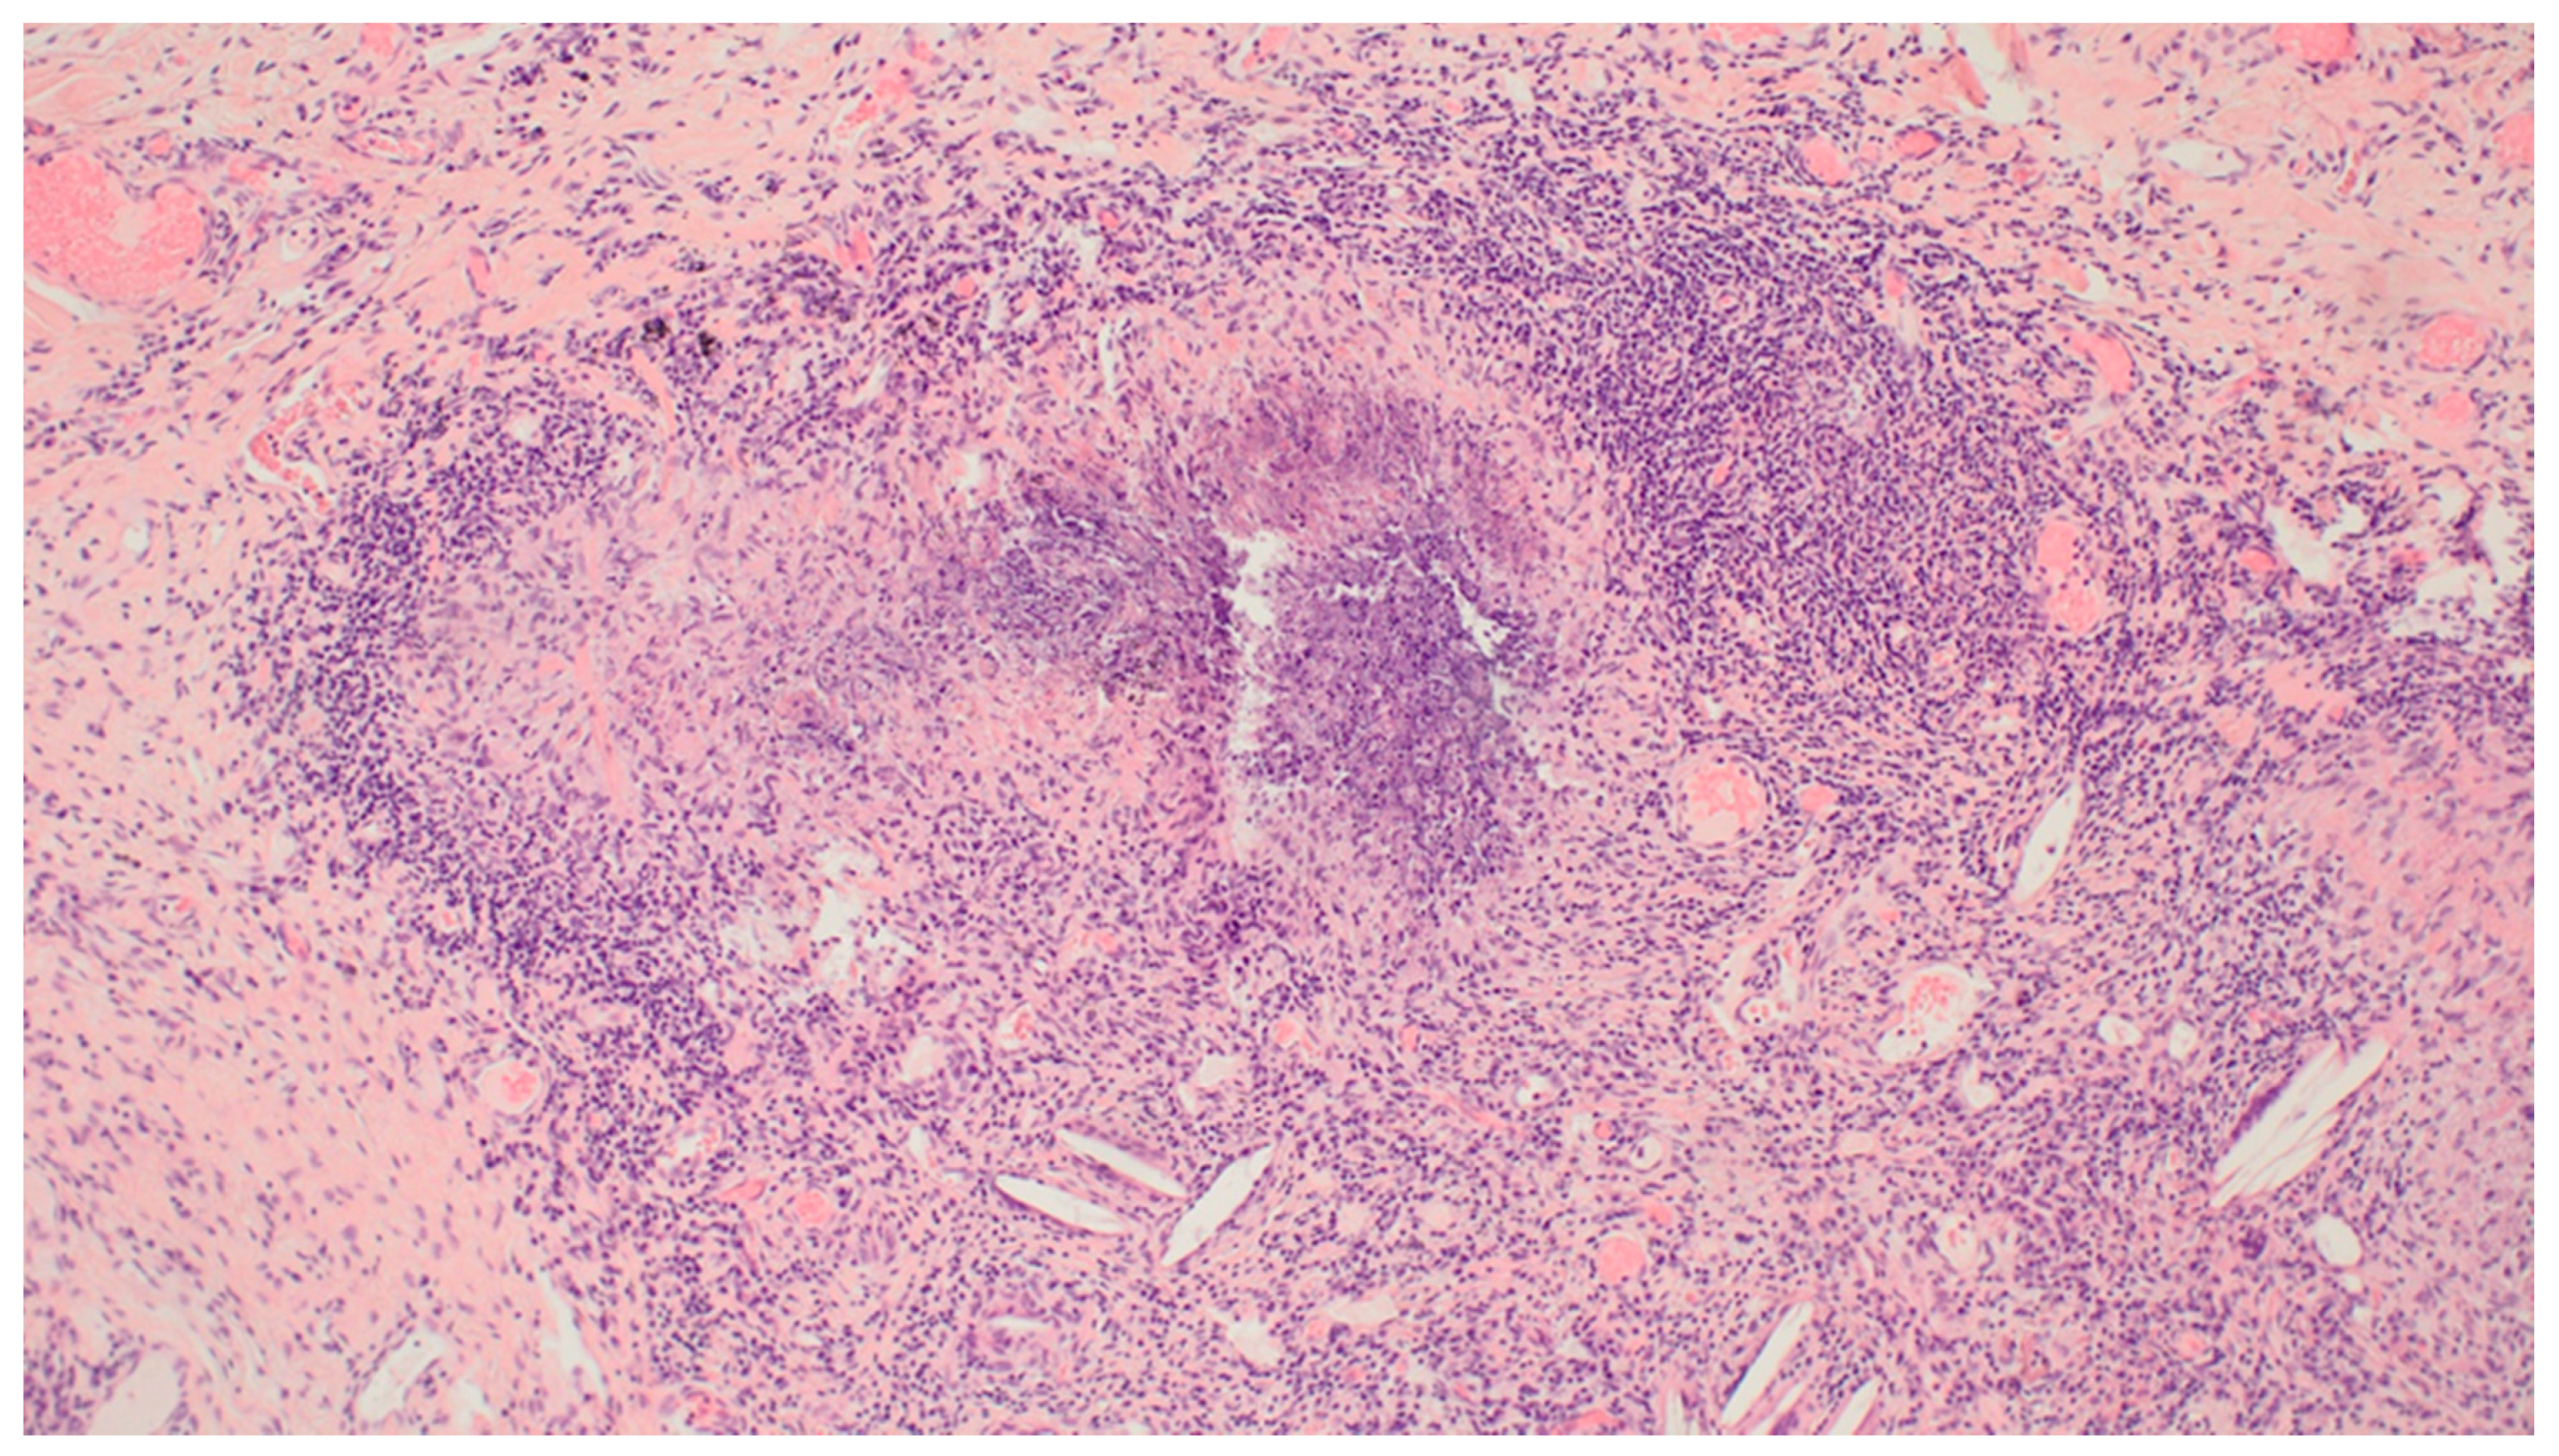

Uncommon Presentation of Granulomatosis with Polyangiitis Mimicking Metastatic Lung Cancer

3. Results